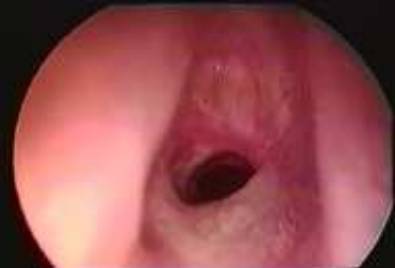

18 下图中所见异常的部位是:

A. 左声带

B.  右声带

C.  会厌

D. 勺状软骨

18A

这左侧声带的瘀斑是一次以可弯曲支气管镜通过声带进入气管的不成功尝试的结 果。会厌在这个图片中是不可见的。双侧声带都清晰可见,并且两者前联合(V的 端点),后联合(喉头宽的联合直观可见。杓状软骨 (这在图片中不可见的)是在这V 字宽底的两端。